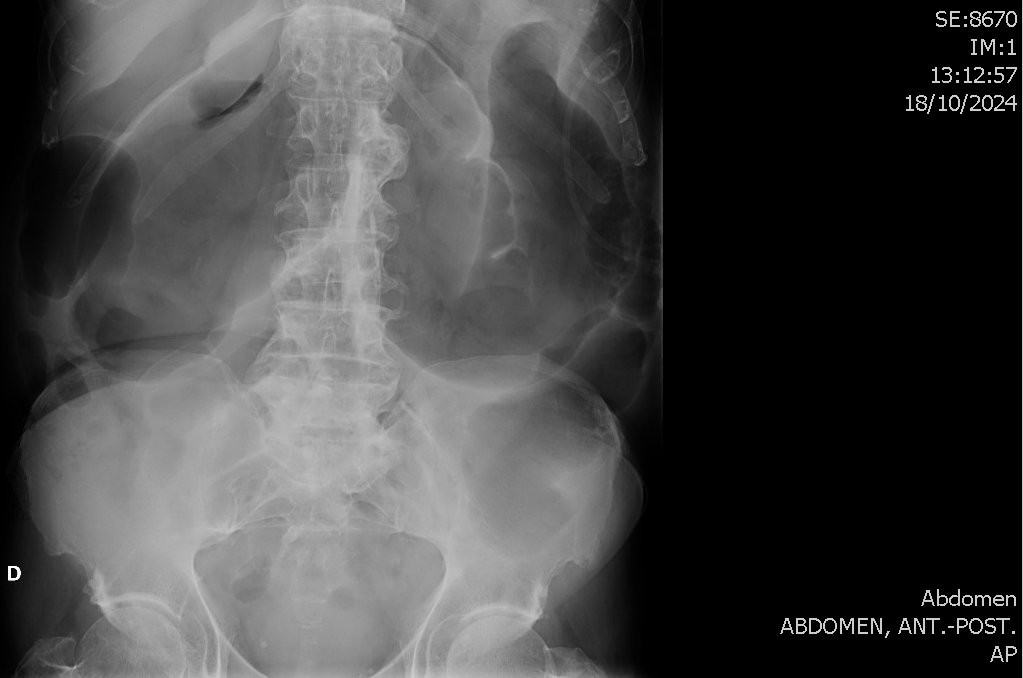

Ante los hallazgos ecográficos derivo a Urgencias Hospitalarias, donde se objetiva un Fracaso Renal Agudo que condiciona el ingreso del paciente. Rx abdominal en bipedestación anodina. Durante el ingreso presenta empeoramiento progresivo de la distensión abdominal objetivable en radiografías seriadas y descartándose obstrucción mediante TC abdominal. Es diagnosticado de megacolon tóxico secundario a infección por Campylobacter jejuni.

Evolución favorable. Persiste leve dilatación sigmoidea en rx realizada 1 mes tras el alta.